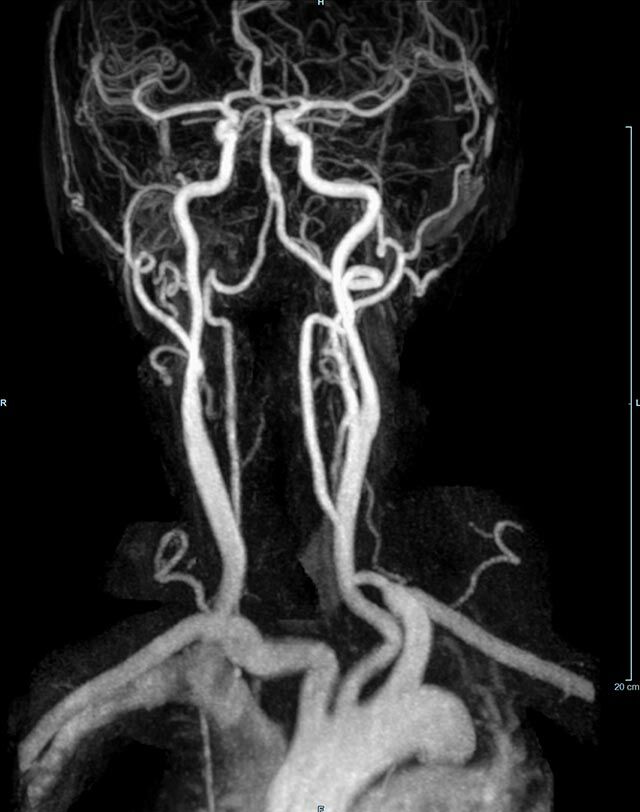

MR-Angiografie (MRA)

• MR-Angiografie ohne Kontrastmittel

• Time of Flight (TOF)-Angiographie

Je nach Fragestellung und Körperregion Gefäßdarstellung ohne Kontrastmittel bei Kontrastmittelunverträglichkeit oder terminaler Niereninsuffizienz möglich.

• MR-Angiographie mit Kontrastmittel

• Erfassung arterieller und venöser Gefäße/Bypässe aller Körperregionen mit 3D-Rekonstruktion